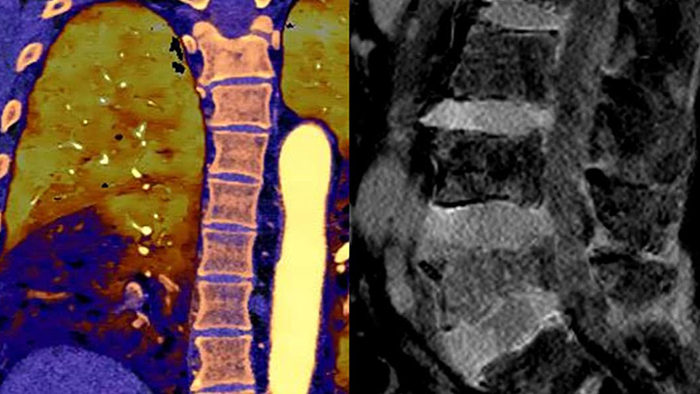

Multi-Energy-CT

2016: Philips - das erste CT-System mit Spektraldetektor

CT-Systeme mit Spektraldetektor machten konventionelles CT zu quantitativem CT. Die zweite Generation des Philips Spectral CT 7500 erhielt den Aunt Minnie Award for Best New Radiology Device in 2021.

Im Gegensatz zur klassischen CT-Untersuchung beinhalten Spektraldetektor-CT-Daten immer auch spektrale Informationen, ohne spezielle Vorkehrungen oder zusätzliche Vorbereitungen. Das bedeutet, Sie können die Spektraldaten jeder Untersuchung auch retrospektiv mit unterschiedlichen Diagnosetools analysieren. Sie können beispielsweise die monoenergetischen Energielevel anpassen oder Z-effektive Bilder erhalten.

Der Spektraldetektor absorbiert und differenziert gleichzeitig die hohe und niedrige Energie eines einzigen polyenergetischen Röntgenstrahls. Spektralergebnisse werden in einem einzigen Scan ohne Einstellung separater Scan-Modi erfasst.

Ein CT-System mit Spektraldetektor absorbiert und differenziert gleichzeitig die hohe und niedrige Energie eines einzigen polyenergetischen Röntgenstrahls auf Detektorebene.